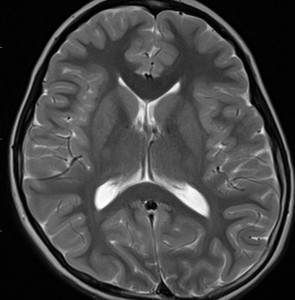

左から,33歳時,35歳時,39歳時の延髄出血です。11歳の時にジャーミノーマで全脳室照射を40グレイ受けました。ジャーミノーマは治ったのですが,延髄左側に海綿状血管腫が22年後に発生して,延髄出血を繰り返しました。もちろん手術などはしません。自然に吸収されてまた落ち着きます。